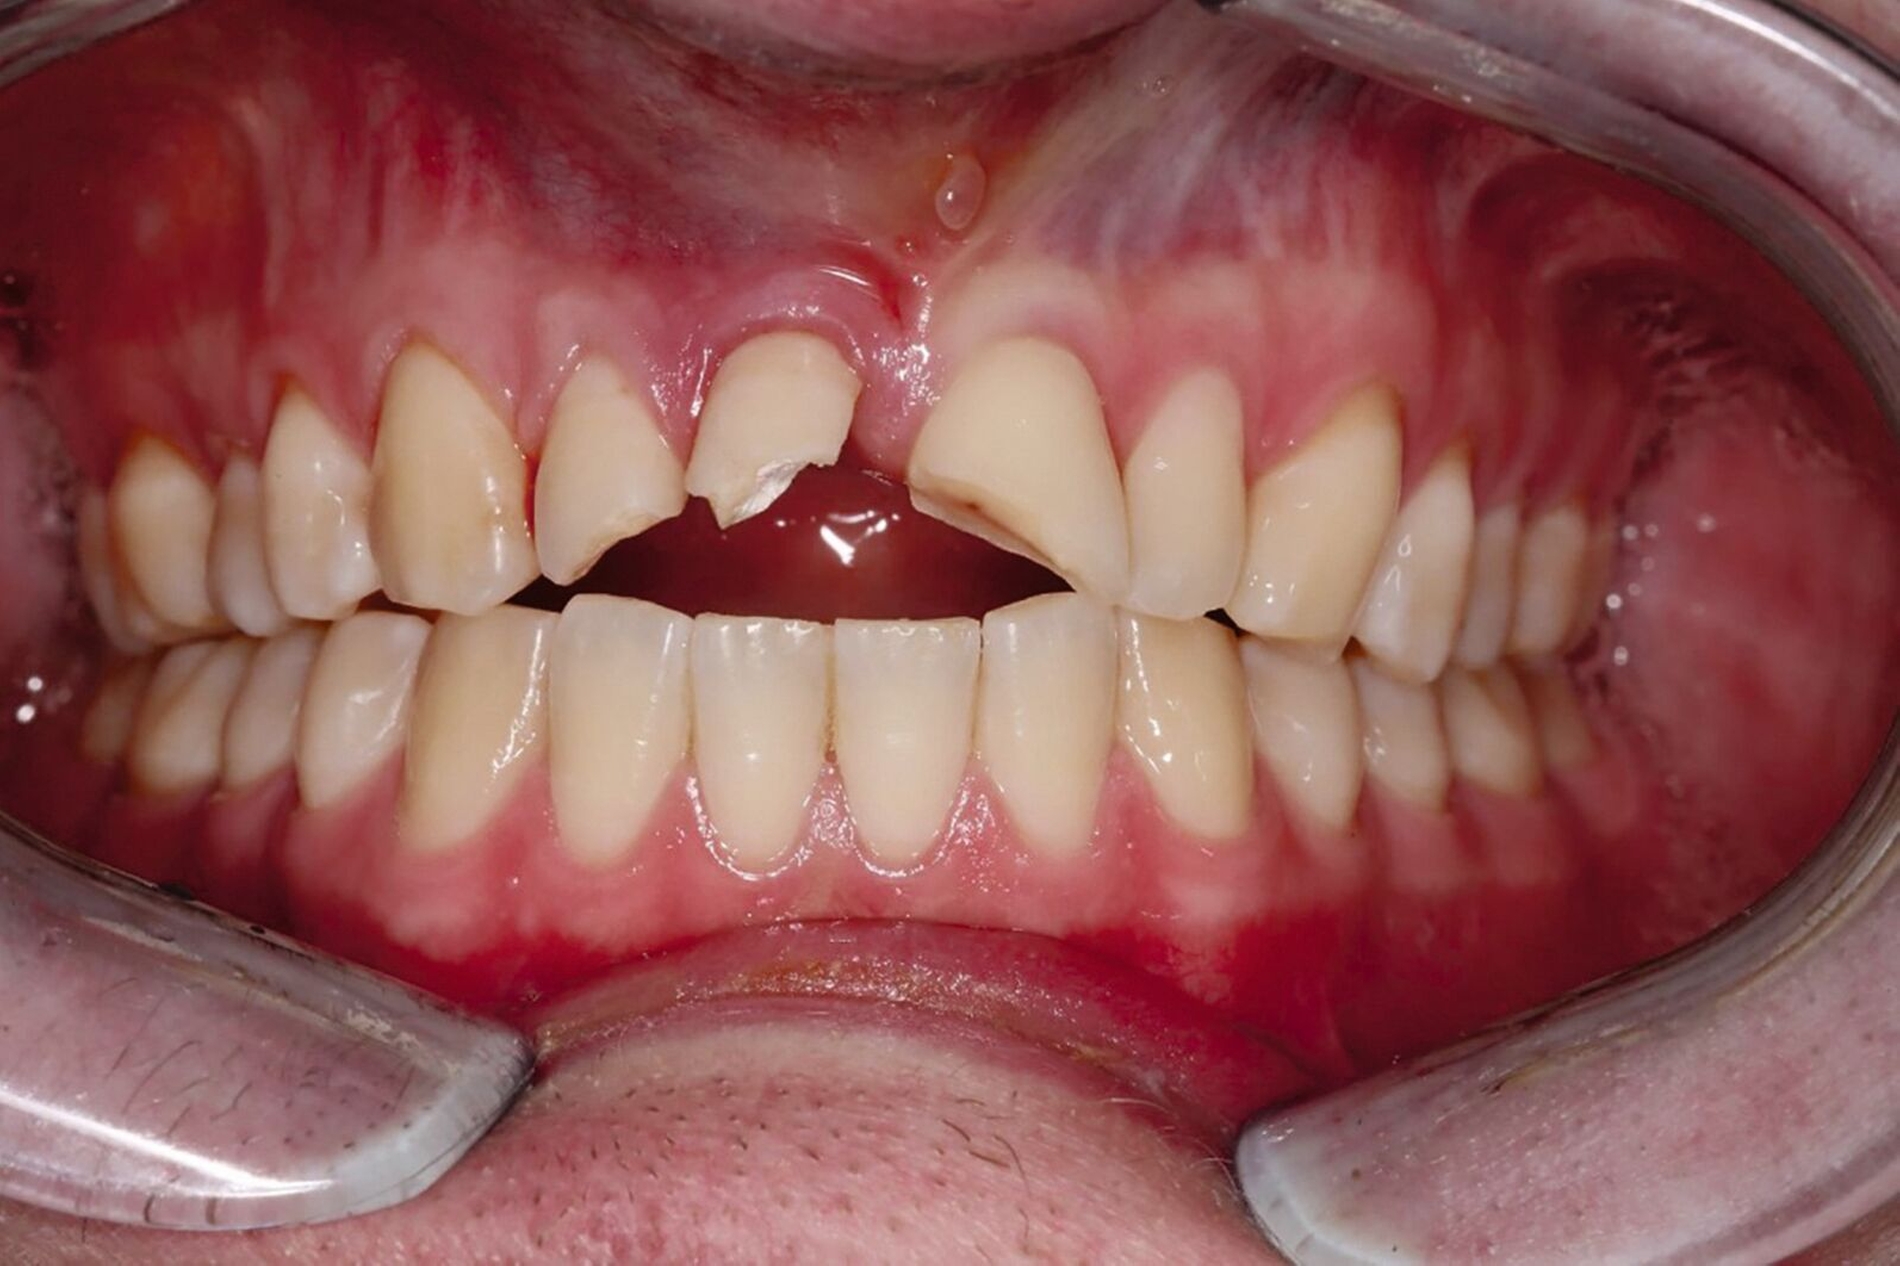

Ein 22-jähriger Patient stellte sich im Februar 2020 im zahnärztlichen Notdienst der Klinik für Zahn-, Mund- und Kieferkrankheiten Mainz vor. Aufgrund einer Synkope war er mit dem Oberkiefer auf den Rand einer Badewanne gestürzt. Intraoral zeigte sich der Zahn 12 mit einer Schmelz-Dentin-Fraktur ohne Pulpabeteiligung (unkomplizierte Kronenfraktur), der Zahn 11 mit einer Kronen-Wurzel-Fraktur mit Pulpabeteiligung und der Zahn 21 mit einer Schmelz-Dentin-Fraktur mit Pulpabeteiligung (komplizierte Kronenfraktur). Die Zähne zeigten keine erhöhten Lockerungsgrade oder Dislokationen (Abbildung 2). Herausfordernd für die weitere Versorgung war der Frakturverlauf an Zahn 11, an dem die Frakturkante palatinal tief subgingival und mesio-palatinal auch subkrestal lag. Röntgenologisch konnte die klinisch gestellte Verdachtsdiagnose bestätigt und eine Wurzelfraktur ausgeschlossen werden (Abbildung 3).